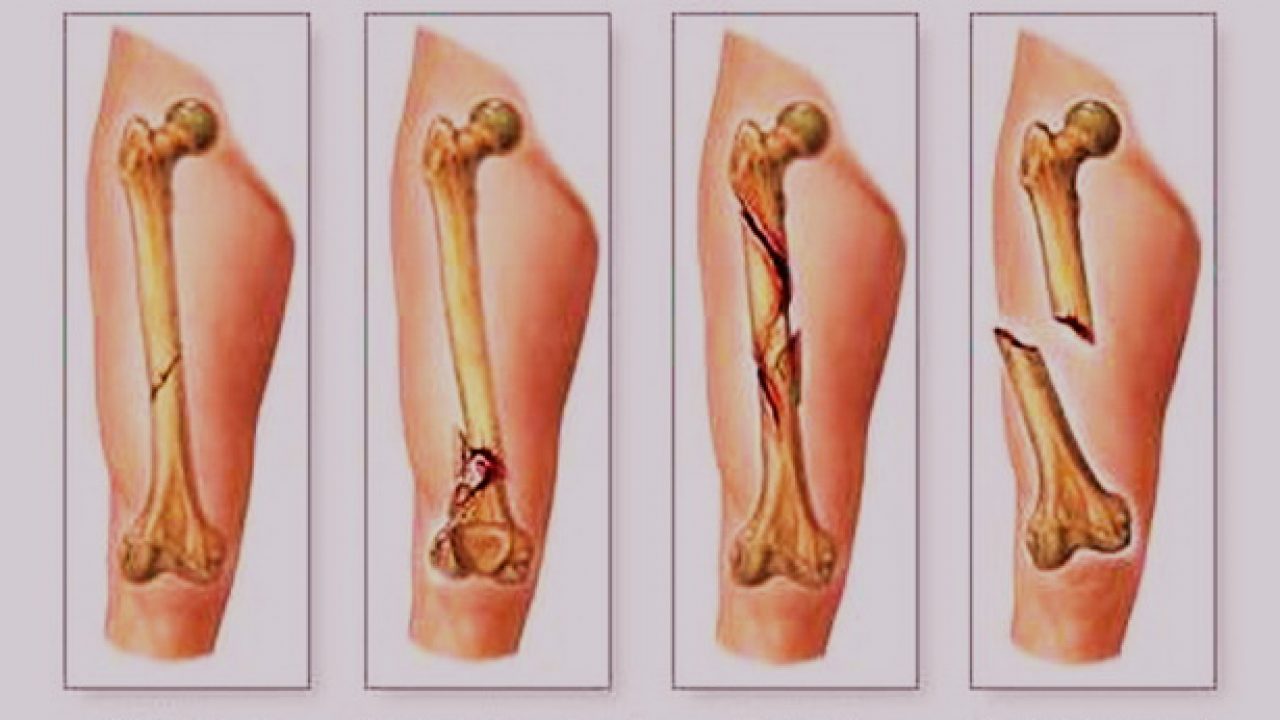

Jenis Dan Kategori Tulang Patah

Jenis Dan Kategori Tulang Patah